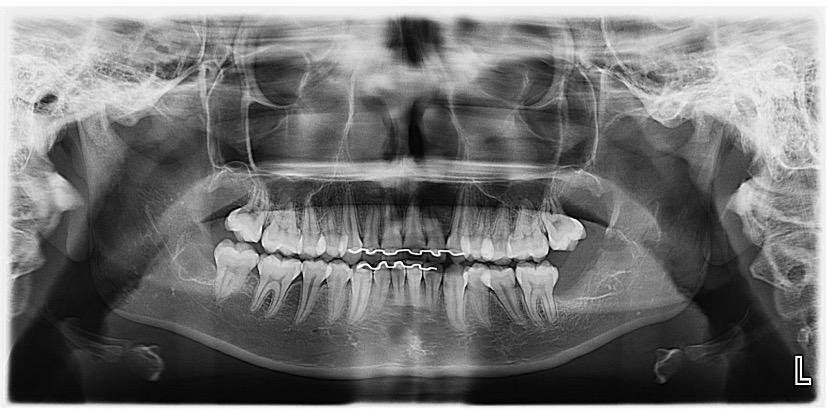

A Patologia Oral e Maxilofacial é a especialidade responsável pelo diagnóstico e tratamento de doenças que afetam a boca, mandíbula e estruturas faciais. Atua na identificação de lesões, cistos e tumores, garantindo diagnóstico preciso e tratamento adequado para preservar a saúde bucal e geral do paciente.